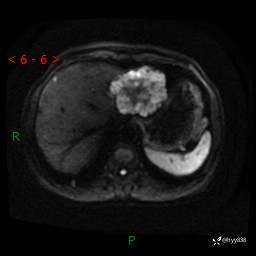

肝脏MRI平扫(同反相位)

T2WIfs+DWI

增强(动脉期+静脉期+延迟期)